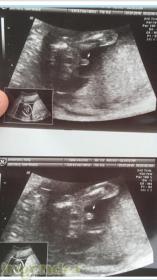

Does this look like a boy nub @ 11+6?

Very early but it looks very boyish.

Very early, but I agree it looks boysh

The stacked nub in first pic makes me think boy. Sometimes a boy nub can image as a girl nub if only part of it is captured, which may be why it isn't captured in the other nub pic. But I hope you get your heart's desire.

First picture has the cord going past the nub so the part on top might be that or maybe stacking. I'm not100% sure